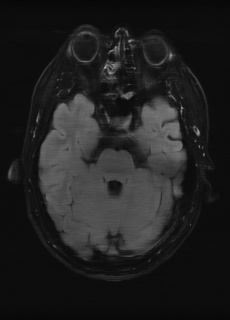

λT1=6.63subscript𝜆subscript𝑇16.63\lambda_{T_{1}}=6.63 Refer to caption (a) 34.38/0.9371 Refer to caption (b) 42.42/0.9883 Refer to caption (c) 44.60/0.9920 Refer to caption (d) 45.50/0.9940 Refer to caption (e) PSNR/SSIM

λT2=2.11subscript𝜆subscript𝑇22.11\lambda_{T_{2}}=2.11 Refer to caption (f) 29.74/0.8903 Refer to caption (g) 36.25/0.9734 Refer to caption (h) 36.42/0.9752 Refer to caption (i) 37.70/0.9832 Refer to caption (j) PSNR/SSIM

λflair=8.00subscript𝜆𝑓𝑙𝑎𝑖𝑟8.00\lambda_{flair}=8.00 Refer to caption (k) 39.89/0.9311 Refer to caption (l) 43.94/0.9864 Refer to caption (m) 44.74/0.9883 Refer to caption (n) 45.49/0.9894 Refer to caption (o) PSNR/SSIM

Figure 3: Visual comparison of different methods, with PSNR (dB) and SSIM values listed under the images. After recovery, the images are shaper with more visible details.